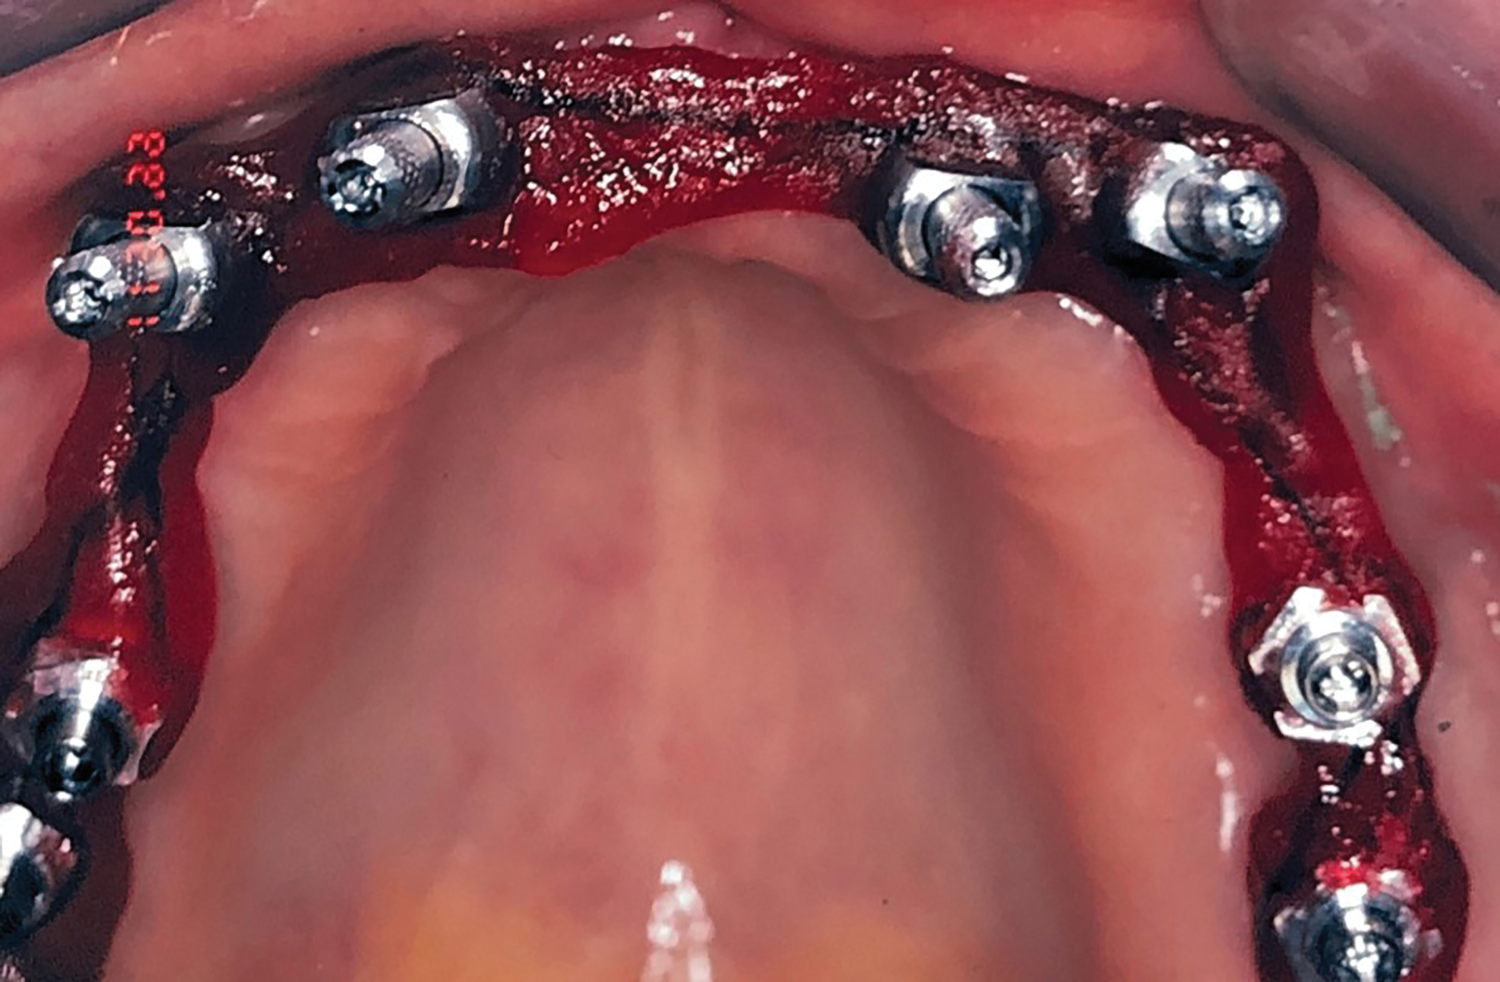

Fig 3. Maxillary arch after placement of TIs.

Figure 3

Placement of Transitional Implants

Teeth Nos. 10, 14, and 15 were extracted after achieving local anesthesia (2% lidocaine with 1:100,000 epinephrine, Henry Schein Dental). Teeth Nos. 6, 11, and 16 were retained as temporary abutments for the provisional. A midcrestal incision was made with a 15C blade, and a full-thickness flap was reflected with a periosteal elevator. Osteotomies were created with a 1.3-mm pilot drill at sites Nos. 3, 5, 8, 9, 12, and 14 using a surgical stent. Six TIs (Dentatus MTI, Dentatus) were placed using a right-angle handpiece driver and then tightened manually with the winged socket key (Figure 3).